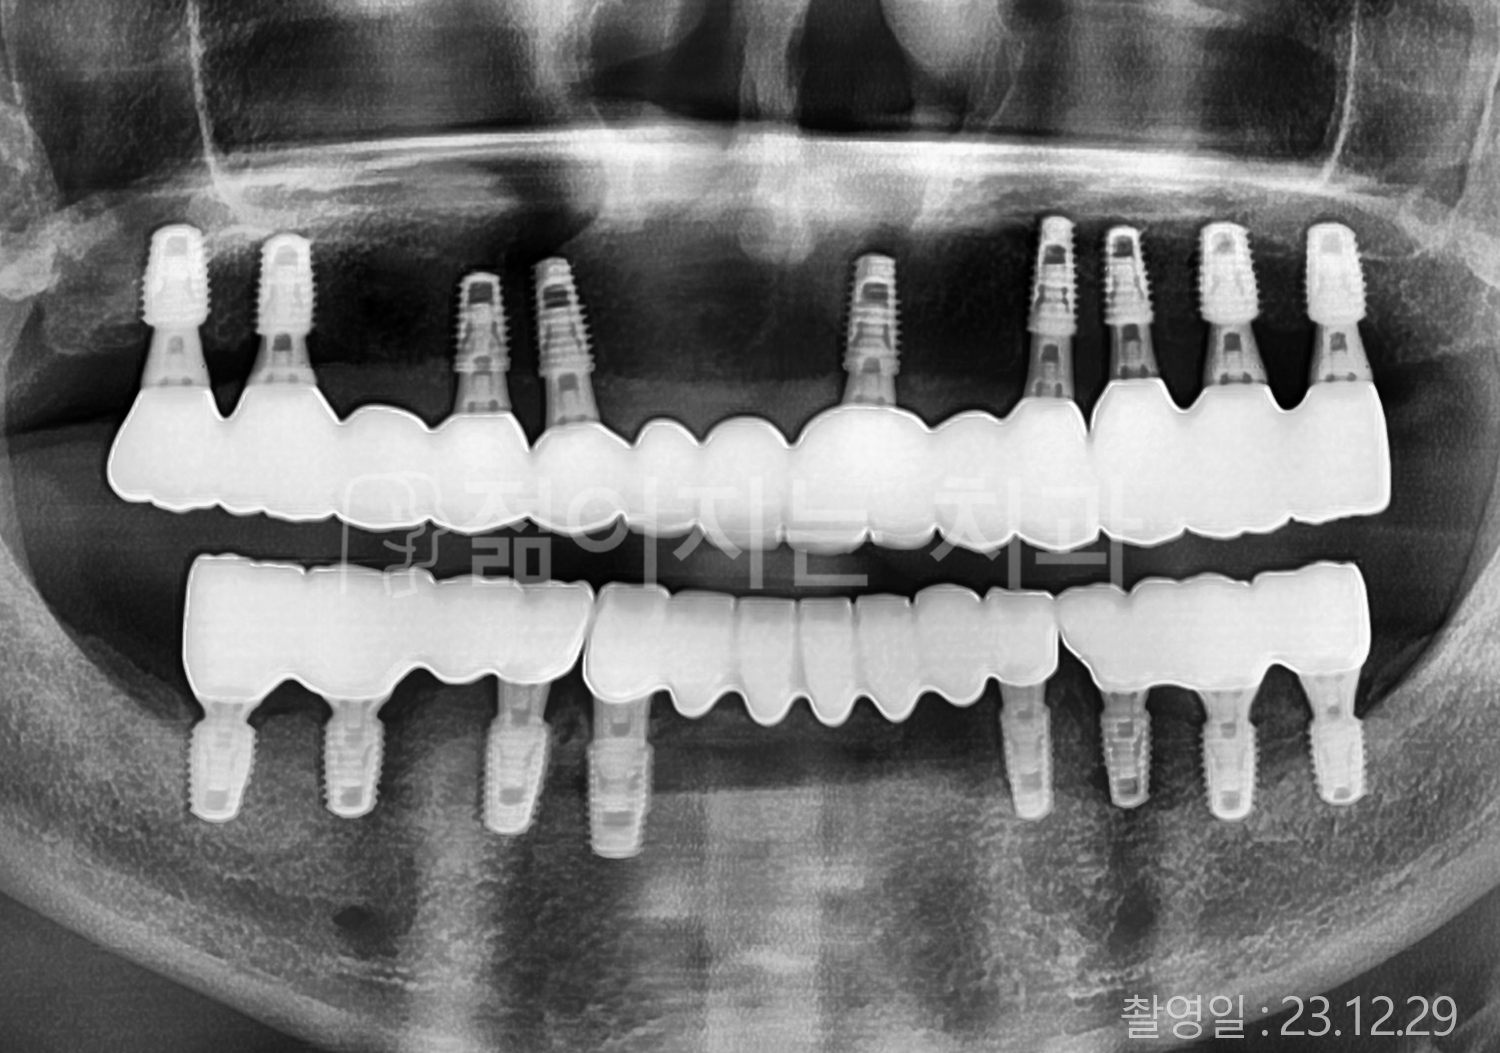

• 70대 고혈압, 당뇨 전체치아 10개 이상 임플란트

• 50대 고혈압, 당뇨 전체치아 10개 이상 임플란트

• 60대 고혈압, 당뇨 전체치아 10개 이상 임플란트

• 50대 전체치아 10개 이상 임플란트

• 70대 당뇨 전체치아 10개 이상 임플란트

• 80대 전체치아 10개 이상 임플란트

• 40대 전체치아 10개 이상 임플란트

• 60대 고협압, 고지혈증 전체치아 10개 이상 임플란트

• 60대 전체치아 10개 이상 임플란트